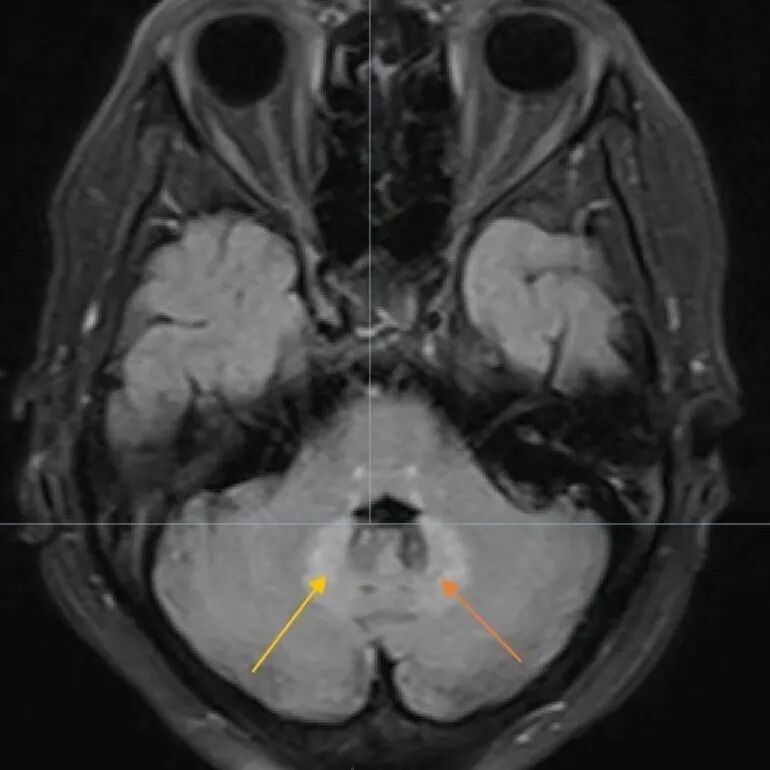

67岁张女士,1月余前无明显诱因出现头晕,症状呈持续性,感行走不稳,视物模糊、恶心。一直未予在意,直到多次出现跌倒才引起重视,遂前往我院神经内四科门诊就诊,并收住院治疗。住院后抽血完善各项化验指标均未见明显异常。完善颈部血管彩超、双下肢血管彩超均无特殊表现。查头部磁共振平扫提示脑内多发缺血及腔隙性梗死灶(慢性期);桥脑及小脑齿状核变性灶;头颈部血管均未明显狭窄。初步考虑是桥脑、小脑病变所致,但仍不能明确是什么原因导致了桥脑、小脑病变。

再次完善脑部磁共振强化,未见肿瘤等疾病,故病因仍不明确。经验丰富的杨立军主任查房时在仔细查阅患者病历资料后,感觉患者脑磁共振图像有些熟悉,似乎在哪儿见过,再次询问患者病史并了解到:患者最近半年因为牙痛,经常服用一种叫甲硝唑的消炎药,立即咨询科内神经内专家高向东主任医师,并调动神内四团队,查阅相关文献资料,最终确定,患者所患疾病为甲硝唑脑病。诊断确立后给予规范化治疗,经过一个疗程治疗,患者头晕、站立不稳症状大部分好转,出院后继续口服药物并进行前庭康复训练后可逐渐康复。

甲硝唑说明书提示,本品可引起神经系统症状,如头痛、眩晕、肢体麻木、共济失调、多发性神经炎等,大剂量可致抽搐。尽管如此,甲硝唑引起的中毒性脑病却鲜为人知。甲硝唑引起的脑病,是由于长期使用甲硝唑引起的不良影响,60%左右是小脑功能障碍,23%左右是精神状态的改变。典型的临床表现如恶心、呕吐、头痛、动作不协调、构音障碍,步态不稳,四肢感觉异常等,MRI常提示脑部出现多个病变信号。停止用药多数是可以好转的,但确切发病原因还尚不明确。